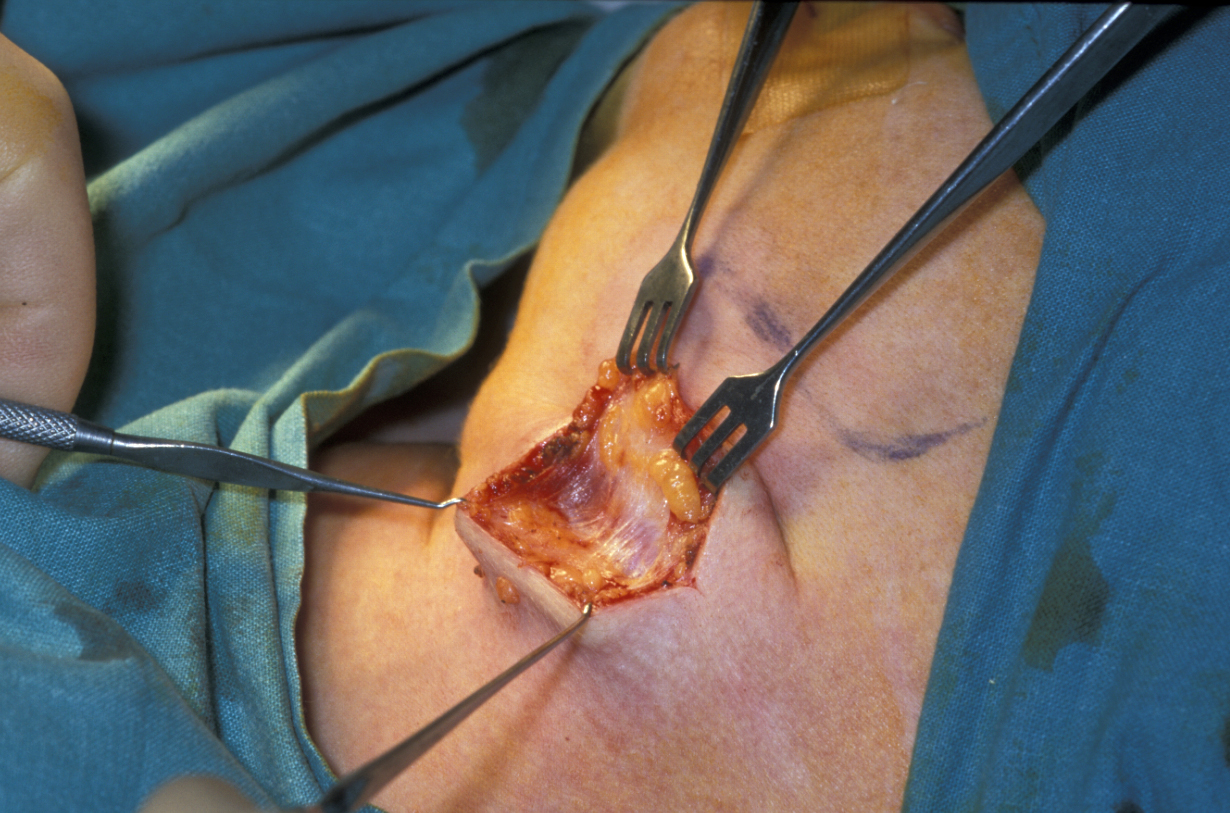

Submandibular gland excision is required after the gland has suffered irreparable damage from infection and/or obstructive disease. The surgical approach is by trans-cervical (from the neck) approach. The incision is two finger-breadths below the lower border of the mandible. A 3 to 4 cm incision is made. The incision is then deepened through fat that bleeds; bleeding needs to be controlled using bipolar diathermy to expose the platysma muscle (a broad sheet of muscle covering front and sides of the neck; see Figure 5).

Figure 5: Submandibular gland excision. The incision is two finger-breadths below the lower border of the mandible. After skin incision, control of bleeding and sweeping aside fat, the platysma muscle is exposed.

Platysma is divided and the lower border of the submandibular gland identified, enveloped in the submandibular fascia. The fascia is incised and an upper flap developed. The flap includes submandibular fascia, platysma, fat and skin. This approach and adhering to the gland will preserve the function of the marginal mandibular branch of the facial nerve. The superficial pole of the gland is mobilised posteriorly (on the back; see Figure 6), if need be by ligating the facial vessels (but this is not always needed), anteriorly by counter-traction and inferiorly by finger dissection.

Figure 6: The submandibular gland lies immediately underneath platysma enveloped in fascia. Sticking to the glandular surface (in glands without tumour) is a safe way to protect the marginal mandibular branch of the facial nerve.